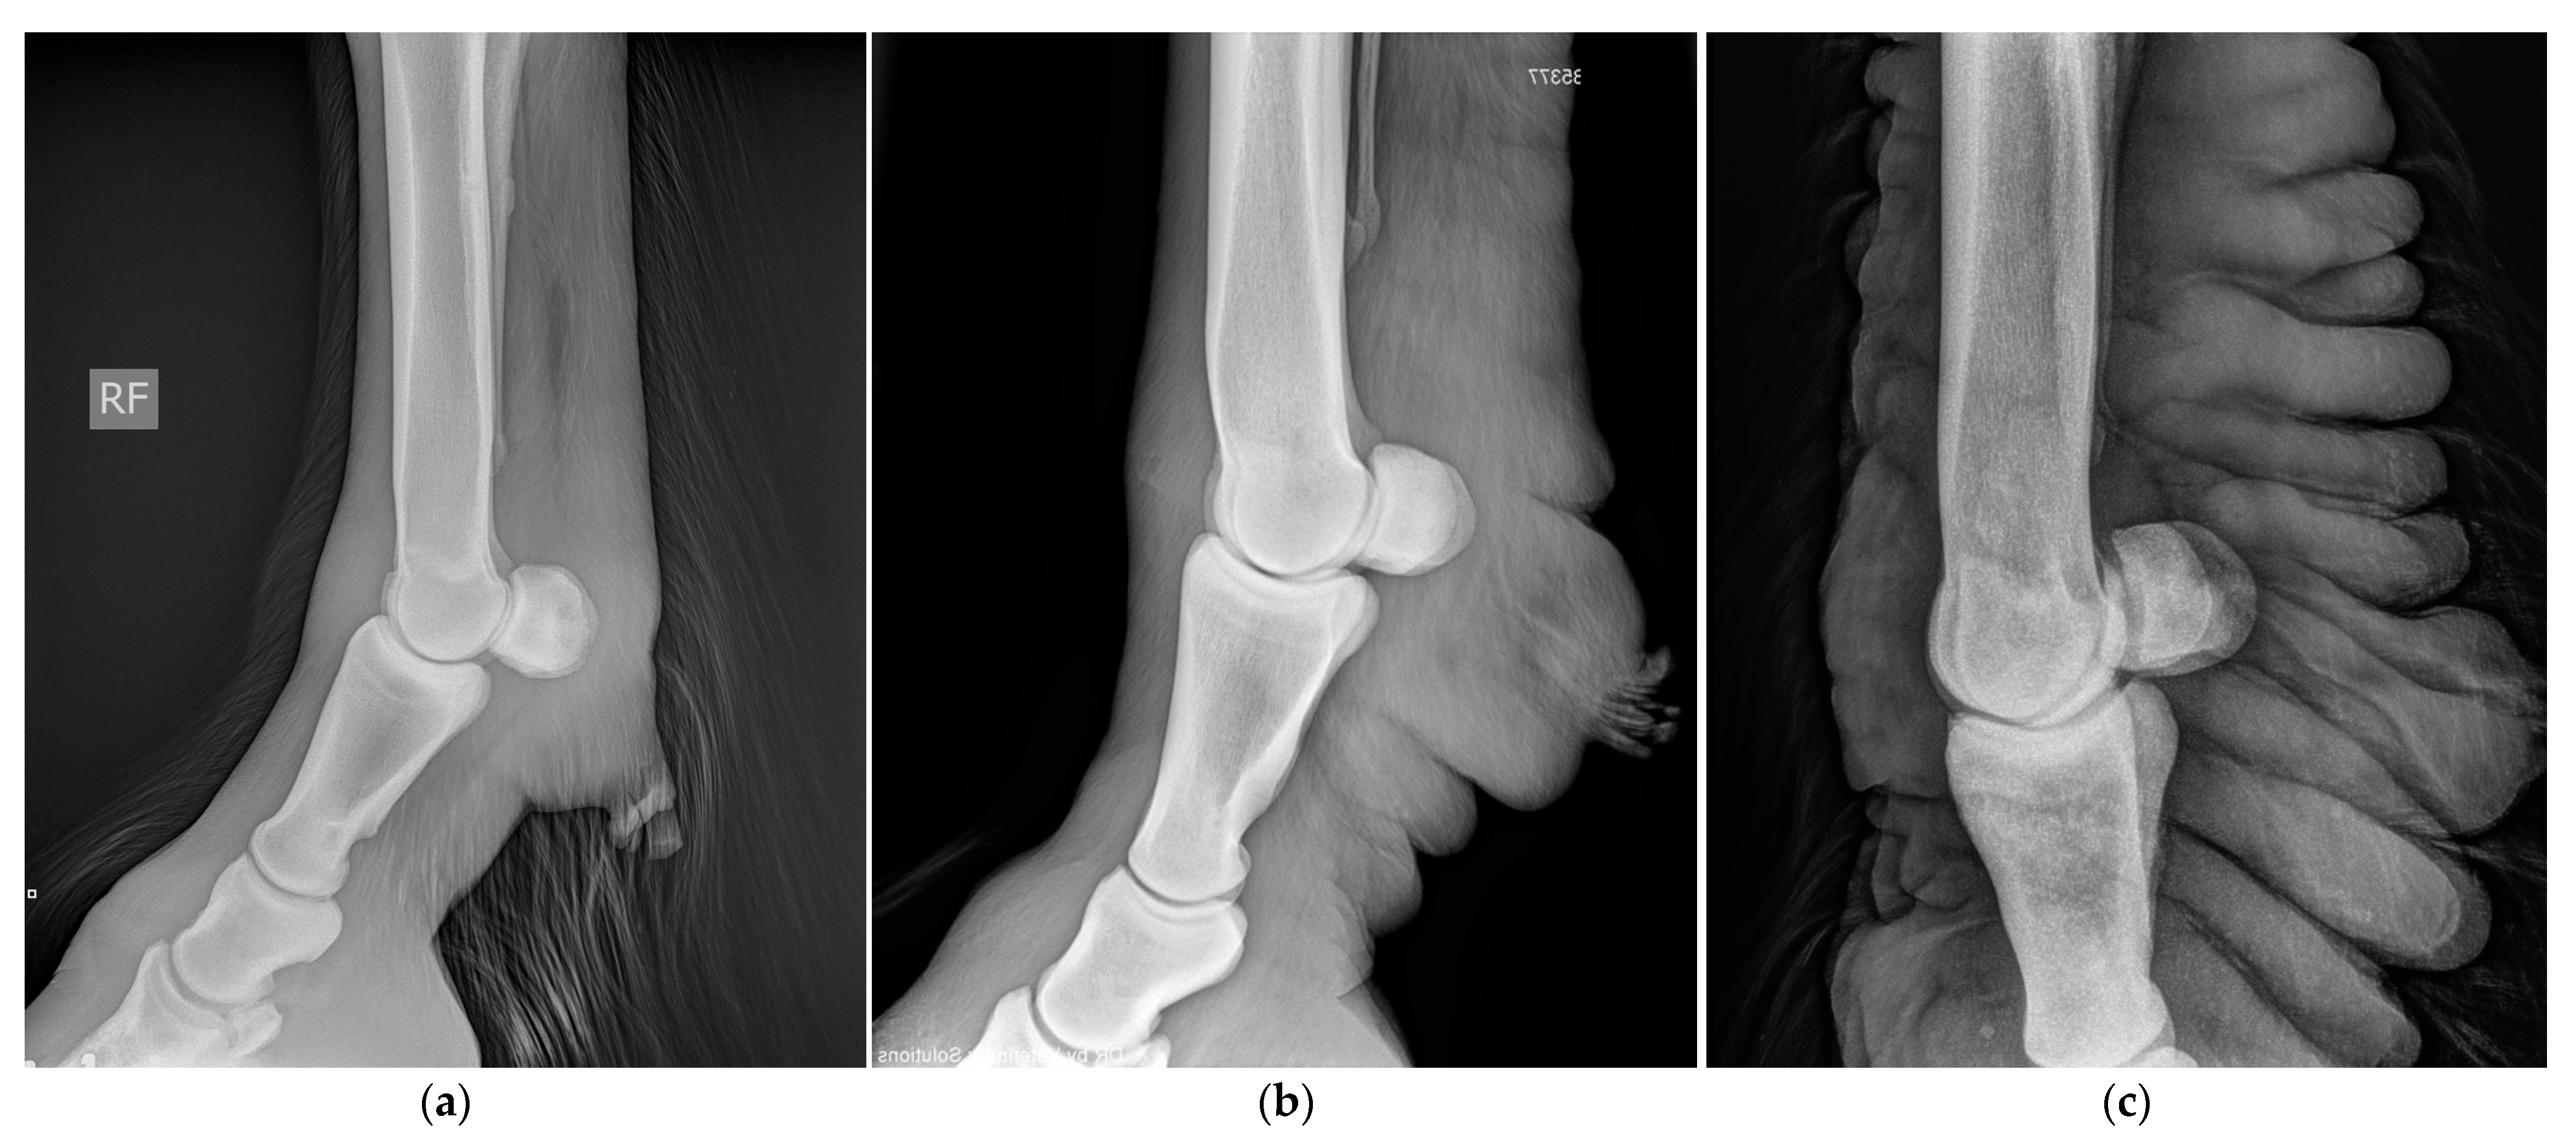

In general, radiographic imaging is considered the most important medical imaging modality for the routine diagnosis of CPL. This technique enables the early detection of skin alterations and provides an important added value in visualizing skinfolds and nodules when palpation is hampered by the presence of abundant feathering on the limbs (Figure 15) [8]. Indirect lymphangiography is a non-invasive technique in which a contrast medium is injected intradermally, followed by radiography to examine the morphology of lymphatic vessels. De Cock et al. have successfully used this technique in draft horses with severe CPL to visualize the tortuous and dilated lymphatic vessels in the distal limbs [6]. In addition, De Cock et al. have demonstrated the presence and severity of lymphatic stasis in CPL-affected draft horses by using lymphoscintigraphy [7]. While lymphoscintigraphy is the method of choice to distinguish lymphedema from other causes of distal-limb swelling in humans, this technique is not routinely used in draft horses.

Figure 15.

Radiographic images of the distal legs in CPL-affected horses. (a) A non-affected Belgian draft horse, displaying no skinfolds. (Courtesy of M. Oosterlinck and K. Vanderperren, 2023). (b) A moderately affected Gypsy Cob mare with clear skinfolds in the pastern region and some slight folding of the skin plantar to the cannon bone. (Courtesy of E. Evrard, 2021) (c) A severely affected draft horse with pronounced, thick skinfolds on the overall distal limb. (Courtesy of Boschhoven paard, 2019).